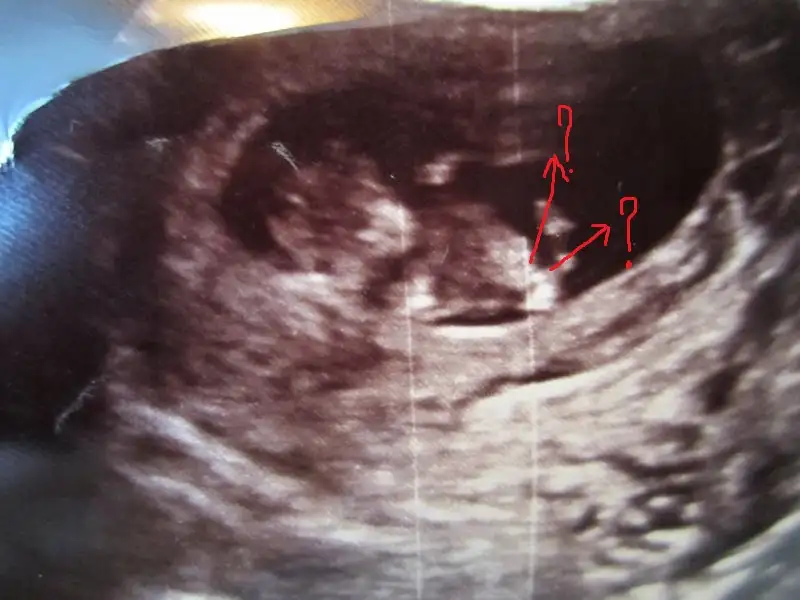

Birde kendim şimdi böyle çizdim doğru yerlerimi yapmışım bakarmısınız ustteki oku şimdi farkettim eger o nubsa erkek diğer sağdaki yatay olansa kız gibi:26: Ayyy şimdi meraklandim iyice

Nub konusunda haksızmıyım bariz bir şekilde paralel görüyorum ben

Nub konusunda haksızmıyım bariz bir şekilde paralel görüyorum ben[/QUOTE]

canim o bacak degil nub karsiya paralel degil yukari bakiyor o nedenle erkek dedim

bu eklemis oldugun nub kiz nubu